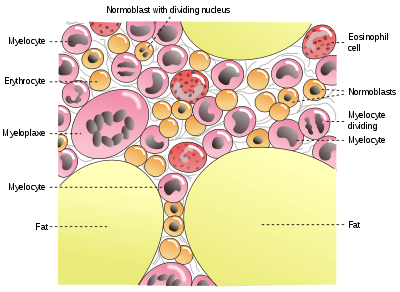

HSCs are found in the bone marrow of adults, specially in the pelvis, femur, and sternum. They are also found in umbilical cord blood and, in small numbers, in peripheral blood.[4]

Stem and progenitor cells can be taken from the pelvis, at the iliac crest, using a needle and syringe.[5] The cells can be removed as liquid (to perform a smear to look at the cell morphology) or they can be removed via a core biopsy (to maintain the architecture or relationship of the cells to each other and to the bone).